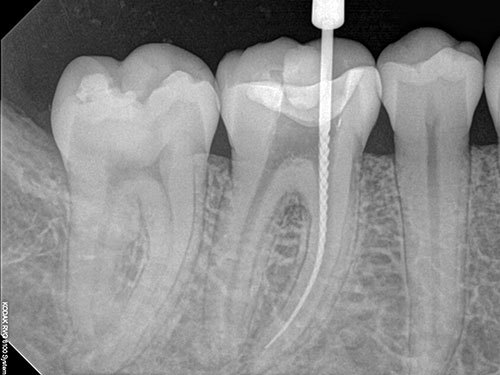

El problema puramente bacteriano de un tratamiento de conductos es solucionable debido al perfeccionamiento de técnica y procedimientos. Esto lo comprueban los éxitos obtenidos por verdaderos artistas en la materia. Se ha visto inclusive que en relativamente corto tiempo, después de un tratamiento de conductos, se normaliza la estructura ósea que presentaba alteraciones comprobadas radiográficamente en terreno periapical. Controles radiográficos repetidos han demostrado lo dicho hasta la saciedad. No obstante tengo que responderle a los que dicen que el tratamiento de conductos perfecto – y les aseguro que no dudo que estas endodoncias existen- es la mejor terapia focal dentógena, que esto en ningún caso equivale a un “saneamiento focal” si efectúan una endodoncia ideal y creen que con ello hicieron un saneamiento focal, están en el error (Raab, 1964) y este error se debe a un mal entendido en la nomenclatura, pues hemos visto que dichos autores (verdaderos expertos en su oficio) entienden por “foco” la alteración periapical radiográficamente visible (el granuloma), mientras que nosotros bajo”foco” tomamos en correcta consecuencia a lo dicho, todo el diente con pulpa muerta, así sea que se presente ahora una curación morfológica reconocible de su osteitis periapical sigue en la boca interfiriendo como “foco intradental” Es también el motivo por el cual rechazamos la amputación apical como terapia focal dentógena.

La exactitud de estos raciocinios recibe su aprobación cientifica en el cuadro clínico de la poliartritis crónica primaria cuya evolución según las experiencias de Altamann y sus discípulos, jamás marchó satisfactoriamente tras las meras eliminaciones de procesos periapicales sino después de la erradicación de todos los dientes con pulpa muerta. Visto de esta manera aparece insostenible la denominación usual de “dientes con foco” o “sin foco” Es mejor hablar solamente de “dientes con pulpa muerta con o sin alteraciones periapicales. Hemos llegado a la conclusión de que el mejor y más aséptico de los rellenos de canales en nada altera el punto álgido de todo suceso focal que no es otro que su componente alérgico neurotóxico.

Respecto del suceso focal, toda endodoncia no es tanto un problema de tratamiento del canal en sí, sino más bien lo que sucede a lo largo y a lo ancho de los canalículos transversos, desde el interior del diente hasta el periodoncio y viceversa. Desde que existe una odontología científica han sido las interrelaciones entre dentina y cemento, objeto de muchísimas investigaciones histológicas. Al principio se le dio especial importancia a la relación entre cemento y dentina, es decir a la unión transversal-pulpa-periodoncio- esto más que todo buscándole un significado práctico a semejante Inter.-relación para apoyar el tratamiento de conducto. Por algún tiempo se excluyó que no existía comunicación alguna a través y más allá de la frontera entre dentina y cemento y se habló inclusive de una barrera impenetrable. Investigaciones histológicas realizadas por W. Pritz (1964)

En cortes micrométricos de dientes humanos y animales permiten reconocer que los canalículos de la dentina llegan hasta el mismísimo limite entre dentina y cemento y que de ninguna manera terminan antes de este limite en forma de vía ciega La función íntima entre dentina y cemento se caracterizó en dichos preparados por inclusiones que producía el cemento en la dentina en forma de trenza, que eran visibles en el límite de las dos sustancias duras. En terreno cemento celulado y en el de los sitios de reabsorción que llegan hasta la dentina, se encontraron anastomosis entre canalículos de la dentina y lagunas de cemento. Estas anastomosis llevan en sí el carácter de una comunicación genuina. No son de ninguna manera estructuras colocadas una sobre o al lado de otra. Las conclusiones a que obligan todos estos hallazgos respecto del tratamiento de canales las resume Pritz diciendo que la frontera entre dentina y cemento de ninguna forma equivale a una barrera impenetrable y que la comprobada comunicación transversal entre pulpa y periodoncio tiene que jugar un papel muy especial en la génesis alérgica de una enfermedad focal.

Pritz (1956) se dio el trabajo de valorar 1000 historias clínicas del año 1952 de pacientes hospitalizados que fueron referidos al departamento clínico de odontología de Altmann. Este material representa sin duda alguna un promedio amplio que alcanza a dar datos suficientes sobre el cuidado dental de toda la población. A 760 pacientes se les hizo una investigación completa clínica y radiológica tanto de la dentadura como de la región maxilomandibular. De 13.546 dientes examinados se encontraron a ala evaluación clínica y radiológica 2.717 con pulpa muerta, lo que equivale a un 20%, cifra que por paciente da un promedio de 3.6 dientes muertos. De los 717 dientes con pulpa muerta se le encontró a 1.887 (69.4) alteraciones radiológicas. De todos los dientes con pulpa muerta habían recibido tratamiento de conducto 1.836 y de éstos presentaban 1.194 (65%) alteraciones radiológicas.

Respecto al alto porcentaje de las alteraciones radiográficas visibles, anota Pritz que entre ellas se encuentran tanto las conocidas alteraciones de la osteitis apical crónica, como ensanchamientos claros y clásicos del espacio periodontal, especialmente aquellos limitados a la parte apical. En aquel entonces F. Proell llamó la atención sobre el hecho de que dichos dientes, en su mayoría, había que considerarlos como infectados. En dientes con pulpa muerta de ubicación solitaria y en aquellos que se hallaban al final de una fila de dientes se encuentra el espacio periodontal de todas maneras ensanchado, debido a las alteraciones en la presión y a los cambios que sufre allí por sobrecarga de masticación. Pues bien, dichas alteraciones no se tuvieron en cuenta para la elaboración del trabajo. Solo se valoraron en ellos las alteraciones apicales. De estas juiciosas investigaciones hemos tenido que concluir que los portadores de dientes con pulpa muerta con o sin tratamiento de conductos, con o sin alteraciones radiológicas comprobables, presentan una morbidez elevada.